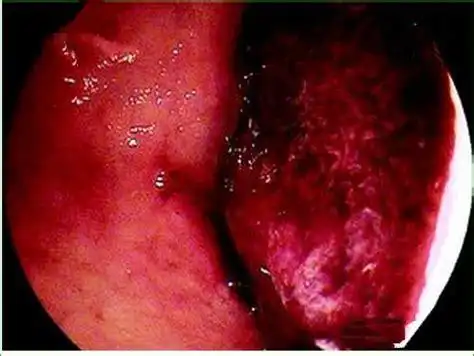

急性糜烂出血性胃炎

惊心动魄的胃溃疡大出血